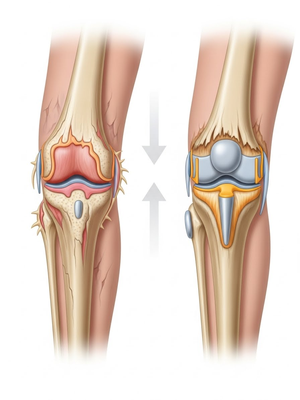

Aşınmış, hasar görmüş ya da eklem yüzeyleri tamamen bozulmuş diz ekleminin, yapay bir eklemle değiştirme işlemidir. Ameliyatta, ağrıya neden olan hasarlı kemik ve kıkırdak dokular çıkarılarak; yerine metal ve özel plastikten yapılmış, uzun ömürlü bir protez yerleştirilir. Bu sayede diz, tekrar ağrısız ve stabil bir şekilde çalışır hale gelir.

Peki total diz protezinde ne yapıyoruz?

Eklem yüzeyleri özel kılavuzlar yardımı ile temizlendikten sonra metal protez eklem yüzeylerine bir kemik çimentosu ile adapte diyoruz. Bu iki metal yüzeyin sürtünmesini azaltmak için polietilenden yapılmış özel bir plastik tabakayı sisteme dahil ediyoruz.